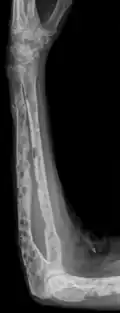

The diagnostic examination of a person with suspected multiple myeloma typically includes a skeletal survey. This is a series of X-rays of the skull, axial skeleton, and proximal long bones. Myeloma activity sometimes appears as "lytic lesions" (with local disappearance of normal bone due to resorption) or as "punched-out lesions" on the skull X-ray ("raindrop skull"). Lesions may also be sclerotic, which is seen as radiodense.[76] Overall, the radiodensity of myeloma is between −30 and 120 Hounsfield units (HU).[77] Magnetic resonance imaging is more sensitive than simple X-rays in the detection of lytic lesions. An MRI may supersede a skeletal survey, especially when vertebral disease is suspected. Occasionally, a CT scan is performed to measure the size of soft-tissue plasmacytomas. Nuclear Medicine Bone scans are typically not of any additional value in the workup of people with myeloma (no new bone formation; lytic lesions not well visualized on nuclear bone scan).

-

X-ray of the forearm, with lytic lesions

X-ray of the forearm, with lytic lesions -